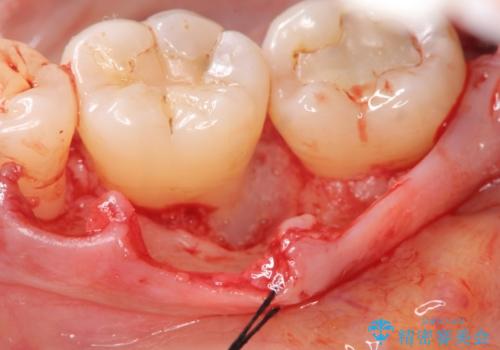

歯周病 再生治療で歯を残す

- 妊娠中に歯周病を指摘・自覚され、出産後に歯周病治療を希望され来院されました。

X線検査、歯周組織検査より歯の周囲の骨が溶ける歯周病であることがわかりました。

歯を抜かずに残せるよう、再生療法・歯周ポケット除去手術を計画します。

再生治療を行うことで、吸収した骨を再生し歯を保存できることがあります。